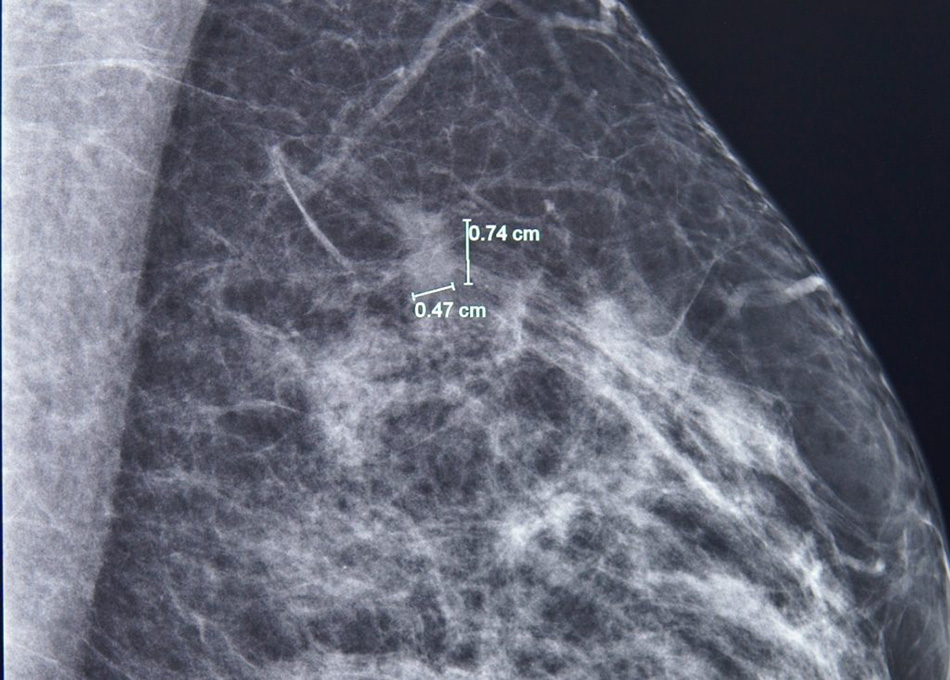

Kết quả nhũ ảnh tìm ra một tổn thương nhỏ, khoảng 7mm ở vú trái. BS.CKI Phùng Ngọc Thư – Trưởng Trung tâm Chăm sóc Tuyến vú FV cho bệnh nhân chụp thêm cộng hưởng từ (MRI) do mô vú bà A. khá đặc, và bác sĩ Thư đã phát hiện thêm một nốt tổn thương khác, chỉ 3mm.

Phát hiện một tổn thương 7mm ở vú trái bằng chụp nhũ ảnh.